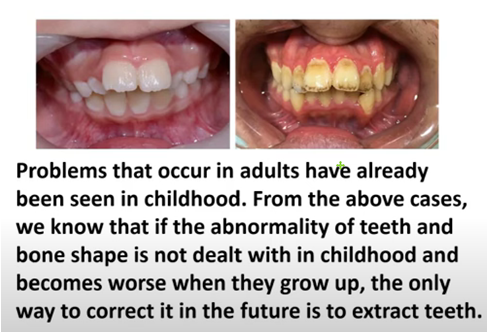

For children with malocclusion or abnormal bones

Orthodontic intervention must be dealt with in a timely manner. However, many parents do not know that bad habits such as mouth breathing and improper tongue positioning are also the main causes of children's irregular teeth. For example, "open bite" is mainly caused by children's bad habits. evolved.

If not treated in time, it will easily lead to

●Biting incorrectly in the future: causing gum recession and bone destruction.

●Deep bite: causing serious wear and tear on the teeth.

●Open bite: This causes wear on the back teeth and worsens the face shape.

●Impacted teeth: cause periodontal disease.

●Tooth gaps: make cleaning difficult.

●Narrow dental arch in the upper jaw: making the teeth messy and difficult to clean.

In addition to the common traditional correction and Invisalign for children, MRC muscle function correction is also an option for early correction treatment. Timely training of oral muscles and the development of the habit of tongue pressing against the roof of the mouth can greatly reduce the error rate of future tooth and palate growth. Grasping the advantages of children's golden period of orthodontics can guide the development of the mandible, provide space for the permanent teeth to sprout, increase the stability of the bite, enhance the self-confidence of growth, reduce the complexity of the second stage of correction, and reduce the probability of tooth extraction in the future.